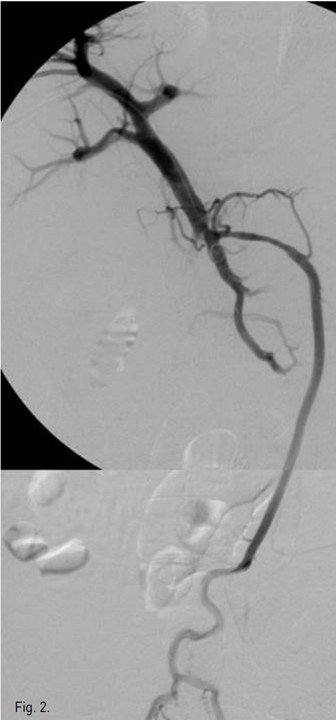

Microcatheter로 superior hemorrhoidal vein을 selection 한 뒤, 양측 vein을 Gelfoam으로 embolization 한 후 flow가 느려졌을 때 2:1(0.5cc glue, 1 cc Lipiodol) glue-lipiodol mixture를 이용하여 embolization 함 (Fig. 4). Completion angiography 에서 IMV로의 flow는 차단되어 보이지 않음. Puncture site 는 2:1 glue로 embolization한 뒤 시술을 종료하였다.

Fig. 4.

Fig. 4. Gelfoam embolization of superior hemorrhoidal vein was followed by embolization with glue-lipiodol mixture (1:2)